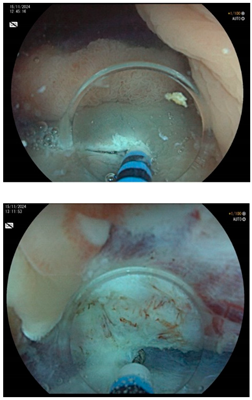

| Endoscopic mucosal resection (EMR) involves injection of a solution into the submucosal space in order to separate the mucosal lesion from the underlying muscularis propria. The lesion can then be resected by snare electrosurgery. The submucosal cushion theoretically reduces the risk of thermal or mechanical injury of the underlying muscularis propria [81]. | ![]() |

| Endoscopic submucosal dissection (ESD) is characterized by three steps: fluid injection into the submucosa in order to swell the lesion from the muscle layer and circumferential cutting of the mucosa surrounding the lesion, followed by dissection of the submucosal connective tissue beneath the lesion (standard technique). The major advantages of this technique in comparison with polypectomy or EMR include control of the resected size and shape, possible en bloc resection even in a large lesion and also resectability of the lesions in case of submucosal fibrosis. Disadvantages include the time-consuming procedure associated with a higher risk of complications (mainly bleeding and perforation) when compared with EMR [83]. | ![]() |